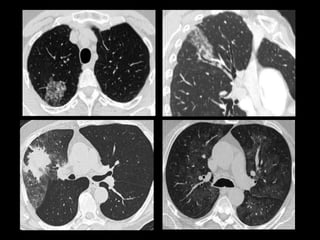

Mujer de 18 años con episodio de hemoptisis con

exploración ORL normal